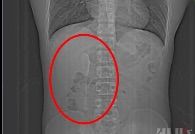

[뉴시스] 중국의 한 20대 남성의 뱃속에서 티스푼이 6개월 만에 발견됐다. (사진=신랑재경 영상 캡처) 2025.6.25 *재판매 및 DB 금지

CT 촬영을 해 보니, 길이 약 15㎝인 숟가락 모양의 물체가 찍힌 것이다.

6개월 간의 위장 운동으로 인해 이 스푼은 십이지장 구부(구부러진 지점)와 하행부(아래 쪽으로 내려가는 지점)의 접합부에 정확하게 꽂혀 있었다고 한다.

이 부위는 구멍이 좁고 장벽이 매우 얇아 이물질이 쉽게 박히고, 주의하지 않으면 천공이 발생하기 쉬운 부분이다.